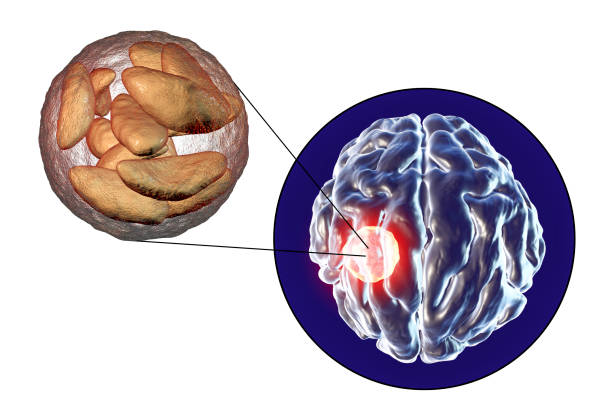

4. 뇌관 부위 손상

뇌관은 우리 몸의 생체 징후를 담당하는 부위로, 이상이 있는 경우 음식을 적절히 소화하지 못하게 되어 식사에 어려움을 겪을 수 있습니다. 호흡 장애도 발생할 수 있어 인공호흡 장치가 필요할 수 있습니다.